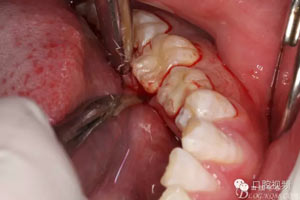

圖5.行齦溝內(nèi)水平切口,不建議做垂直附加切口,因?yàn)榭诘捉M織淺,容易水腫。風(fēng)險(xiǎn)大。

圖6.翻瓣、形成袋形瓣